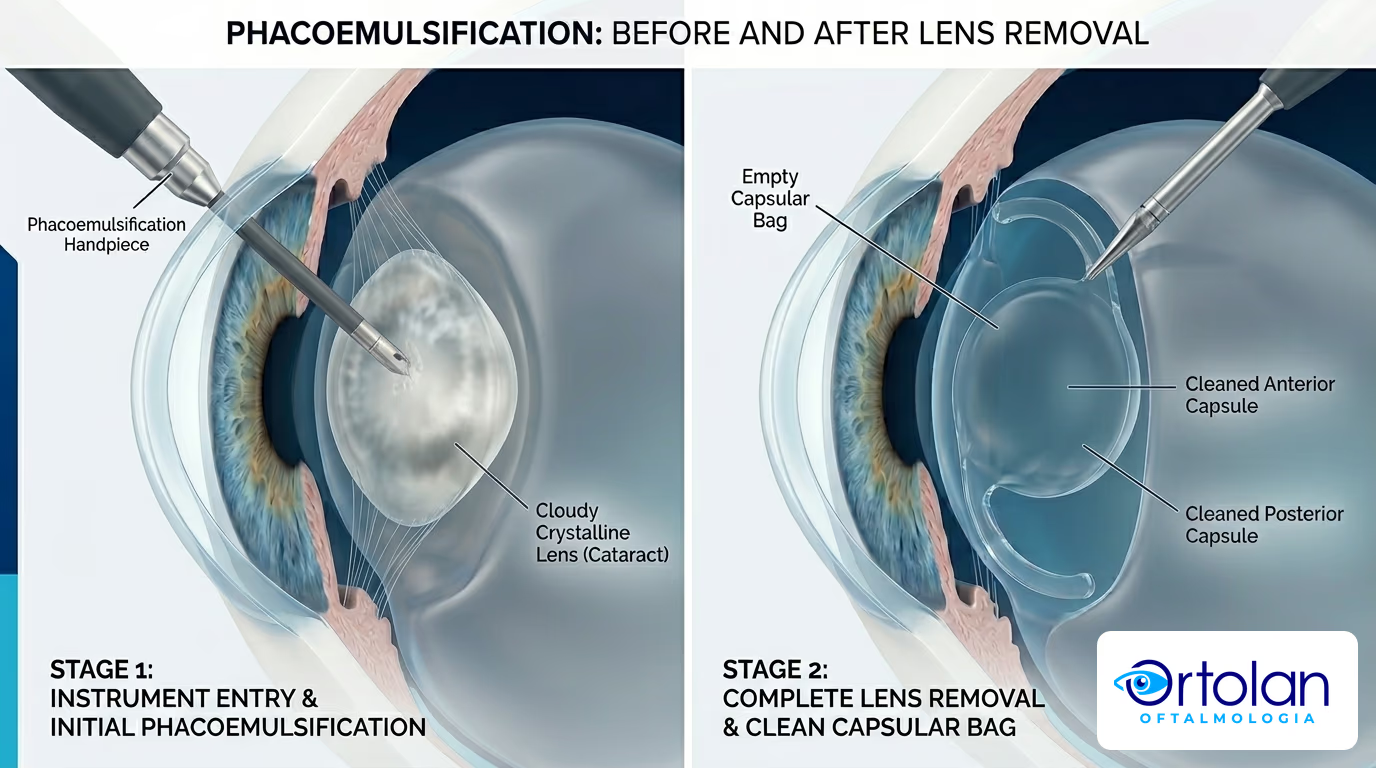

Facoemulsificação: a técnica moderna

A técnica padrão hoje é a facoemulsificação. O ultrassom quebra o cristalino opaco em pedaços minúsculos. Esses fragmentos são aspirados por uma microincisão de cerca de 2,2 a 2,4 mm. Pela mesma abertura, o cirurgião implanta a lente intraocular dobrável.